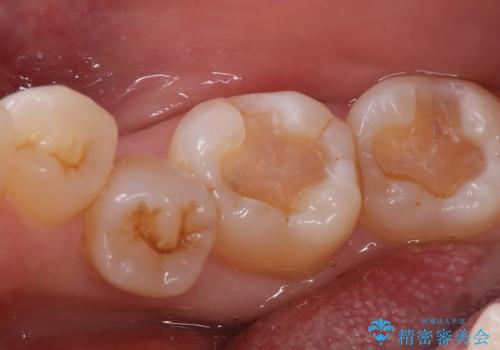

- 主訴:口を開けると所々入っている銀の詰め物が目立つので白い物にやり替えたい。

下顎大臼歯部に入っている保険適用のメタルインレーを、適合性と審美性の良いセラミックインレーでのやり替えとなりました。

メタルインレーを除去した際、古い裏層材やカリエスは除去し新たにCR裏層しています。